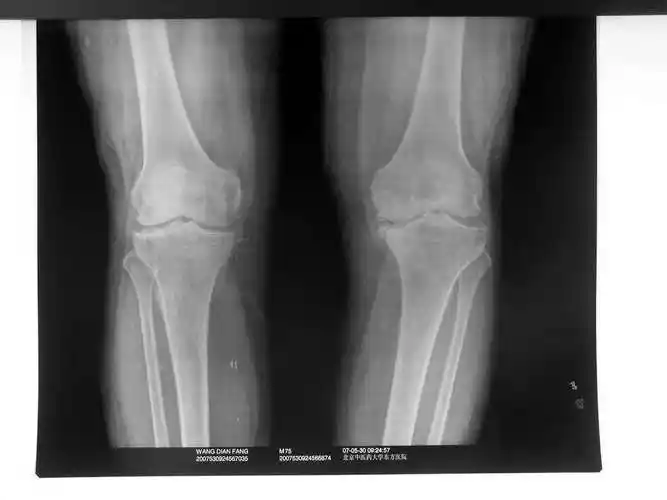

膝关节影像

各位高手请帮忙看下一张膝关节平片

dr和ct可以清晰地显示骨质的形态及结构,可以判断是否存在骨质疏松